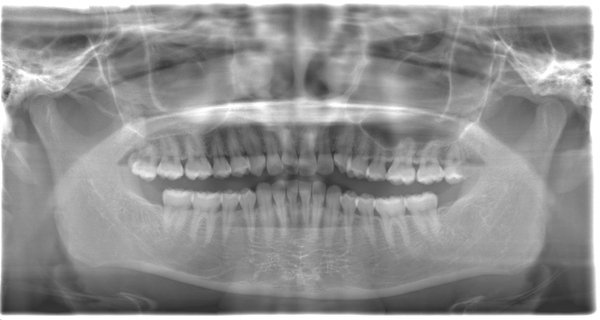

CASE 10

| 年齢・性別 | 39歳・男性 |

| 主訴 | 左上下親知らず抜きたい |

| 抜歯期間 | 30分 |

| 抜歯費用 | 約2,500円(保険内) 別途CT撮影で3,000円 (2022年7月現在) |

| 抜歯内容 | 左上下の親知らず抜歯 |

| 治療方針 |

親知らずは抜いたほうが良い認識はあったものの、痛みや腫れが出ることを知って、勇気が出ないままでいたとのことでした。 そのまま放置していたら虫歯になってしまい、今回ご来院されました。しっかりと麻酔をして緊張をほぐしながら抜歯を始めました。完全萌出のため、時間を要することなくすぐに抜歯することができました。 |